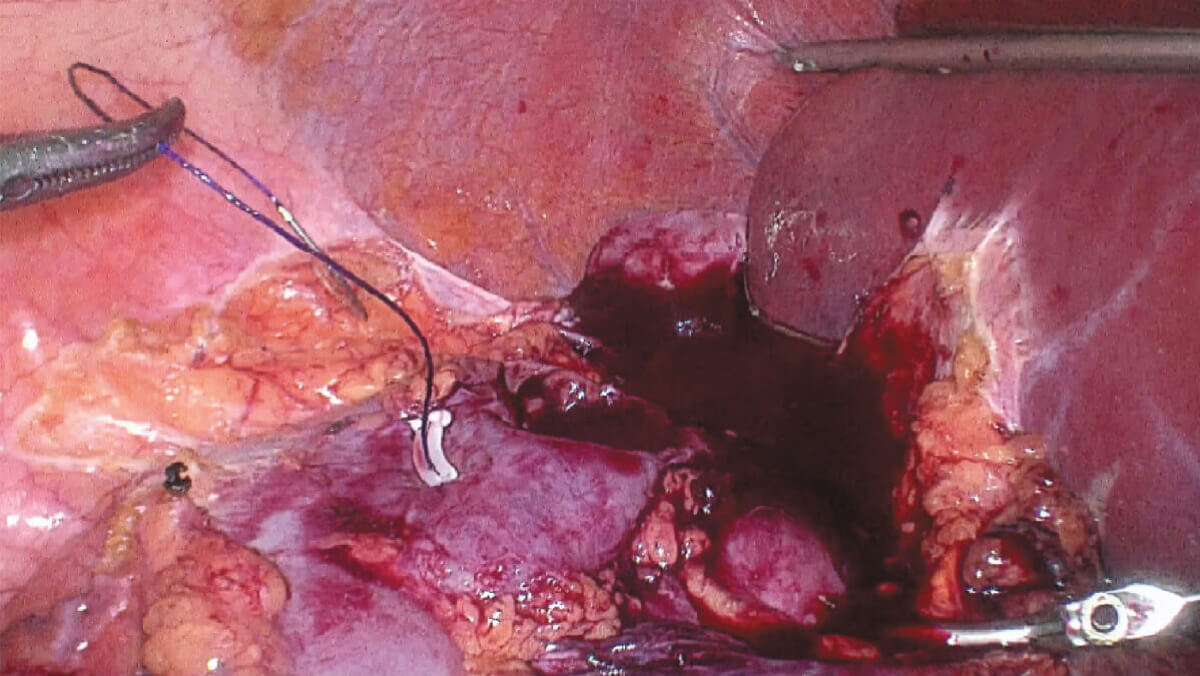

表面细节不遮盖

边界清晰,利于切缘评估

细微结构无伪影

避免术中误伤

荧光信号强弱分明

精准辅助临床决策

术中实时多维导航,领航诊疗一体新标准